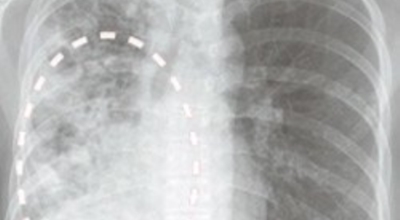

흉부 단층촬영(CT) 계산

임상적으로 의심스럽긴 하지만 흉부 X선만으로 결핵을 진단하기 어려울 때는 컴퓨터단층촬영(CT)이 유용해요. CT는 오래된 섬유화 병변과 새로운 활성화 병변을 구별하는 데 도움이 되고, 보통과 다르게 작은 기관지나 작은 기관지 주변의 병변은 결핵이 시작된다는 것을 특징으로 제시한다('나무 싹 패턴'). 그리고 CT는 충치진단, 흉곽림프절질환, 결핵(세균성 결핵이 전신에 퍼져 가지가지 장기에 염증을 유발한다), 기관지확장, 기관지협착, 흉막질환 등에 대한 민감도가 높아 결핵에 석회의 침전이 있는지 여부를 판단하는 데 아주 유용해요.